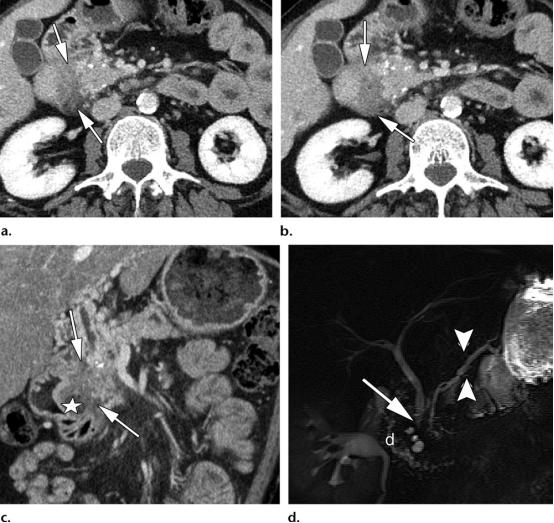

39岁男性,1型实性十二指肠旁胰腺炎(PDP,即沟槽性胰腺炎)

(a图,b图)轴位CT示边界不清的低密度肿物样病变,位于十二指肠胰腺沟内(白色长箭头),胰头区可见散在的胰腺实质钙化灶。

(c图)冠状位CT图示十二指肠沟内肿物样病变(白色长箭头),以及十二指肠壁的囊性变(白色五角星),胆总管远端部分可见。

(d图)磁共振胆胰管成像示胆总管远端局灶狭窄(白色长箭头),胰腺分支胰管略微显著(白色短箭头),关注观察十二指肠胰腺沟的增宽,以及十二指肠壁的囊性变(白色字母d)。

41岁男性,1型实性十二指肠旁胰腺炎/沟槽性胰腺炎,

(a图)轴位压脂T2WI示十二指肠内侧壁的边界不清的肿物样增厚,呈等信号影(白色长箭头),同时患者有十二指肠出口梗阻,关注观察扩张的胃(白色五角星)

(b图)轴位压脂T2WI示胰腺头部以实性为主的肿物样区域,沿十二指肠壁的微囊性病变(白色长箭头)。